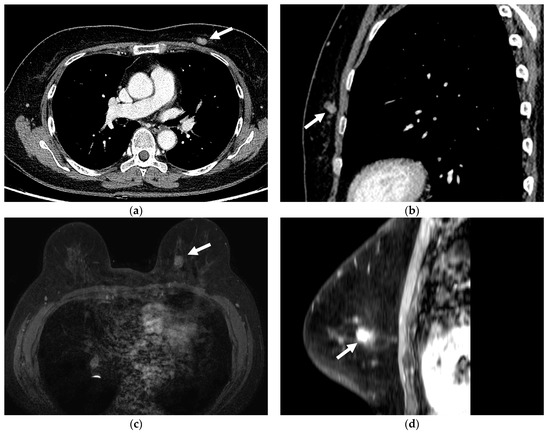

Missed and Detected Incidental Breast Cancers on Contrast Enhanced Chest CT: Detection Rates and CT Features

3.2. Imaging Features of Missed and Detected Breast Cancers

3.3. Imaging Features Associated with Missed Breast Lesions Group